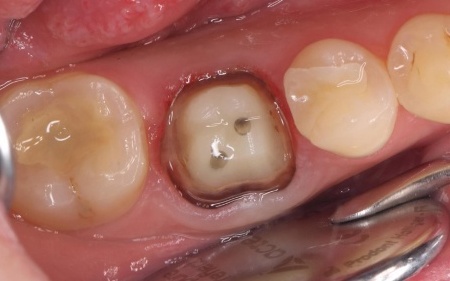

30代女性 破折した古い被せ物を除去してジルコニアクラウンで修復した症例

拝見したところ、右下奥歯に装着されていた被せ物が、経年劣化による強度の低下で大きく破折していました。

このまま放置すると、奥歯でしっかり噛むことができないだけでなく、欠けた被せ物で舌が傷つくおそれがあります。

さらに、歯と被せ物の隙間から細菌や食べかすが入り込み、虫歯が再発するリスクもあるため、早急に被せ物を修復する必要があると診断しました。

欠けた被せ物は10年以上前に治療した部位とのことで、材質はセラミックの一種であるポーセレンだと考えられます。

再び破折する危険性を考慮して、セラミックの中でも人工ダイヤモンドと呼ばれるほど高い強度をもつ「ジルコニア」での修復を提案し、同意いただきました。

まずは右下奥歯の古い被せ物を除去し、歯の形を丁寧に整えます。